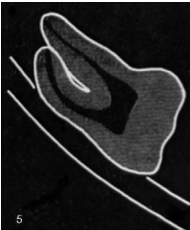

what is this?

Narrowing of the root